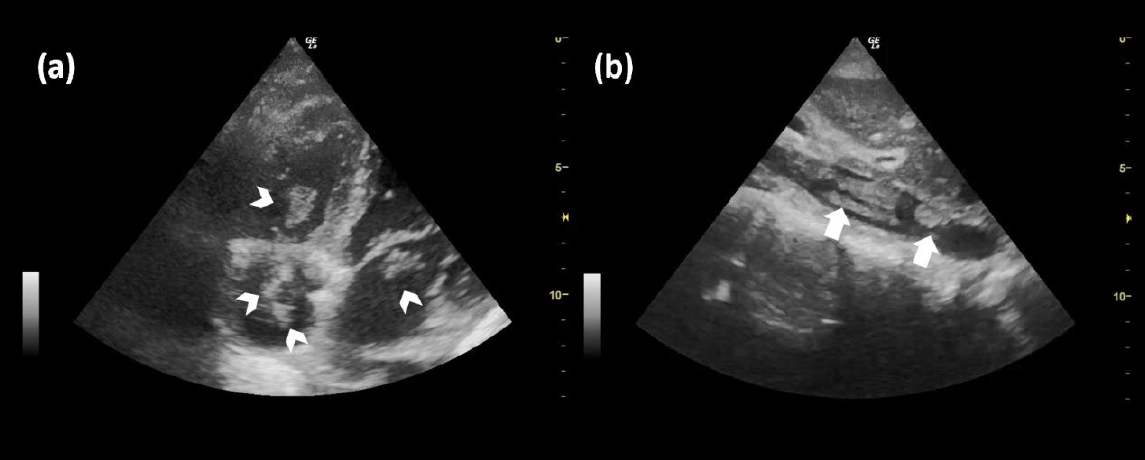

一位 34 歲經產婦(G6P4A1),因胎位不正於妊娠 37 週時在診所接受剖腹產。胎兒出生約 5 分鐘後,產婦產生突發性低血氧與抽搐,隨即心跳停止。經醫師立即實施心肺復甦後轉送急診。到院心率呈無脈搏電氣活動PEA,經 20 分鐘急救後恢復自發循環ROSC。POCUS顯示左心室收縮功能嚴重低下(EF 約 20%),且在心臟四個腔室內皆可見血栓形成,下腔靜脈亦有血栓(圖1)。

圖1. (a)顯示四個心腔內皆可見多發性血栓(箭頭所示)。劍突下下腔靜脈切面影像; (b)可見下腔靜脈內多發性血栓(短箭頭所示)。

本圖取自 Chiu P-W 等人發表於 Annals of Emergency Medicine(2023),經 Elsevier 授權重製